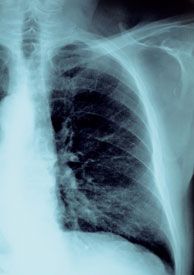

Amid wide variation in treatment practices, the American Society for Radiation Oncology (ASTRO) has for the first time issued its own extensive guidelines for the use of palliative thoracic radiotherapy in patients with metastatic lung cancer.

The guidelines involve treatment approaches to palliative care for patients whose cancer has spread and who are experiencing symptoms such as coughing, shortness of breath, bronchial obstruction, and chest pain.